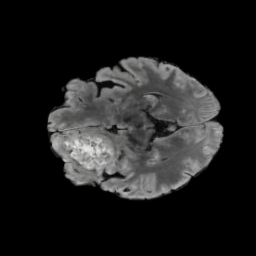

Tumour Information Preservation. For the brain tumor segmentation, we use a Swin UNETR model[27, 70], trained with random rotation, and intensity as data augmentation. In Figure 5, we highlight the tumor profiles of the generated MRIs compared to the ground truth tumour profile. In the test set with human ground-truth annotations (), the real MRI Dice score is 85.15 while the generated MRIs from a single slice have a dice score of 83.09. This shows how the generated MRIs indeed preserve the tumor information and can act as an affordable and informative pseudo-MRI, before conducting an actual costly MRI examination in hospitals.

B.4 Tumour Information Preservation

On the test set with human ground-truth annotations (), the brain volumes generated from single slice input preserve the volume of the different tumour components (paired t-test, for all 3 classes) (see Table 3). The real MRI Dice scores are put for reference to our generated MRIs. X-Diffusion outperforms baselines TPDM [36] and ScoreMRI [18] in tumour preservation (see Table 3 and Figure 12). We ran experiments comparing the tumour segmentation Dice Score varying X-Diffusion configurations. The multi-slice input X-Diffusion achieves a marginally better Dice Score than the single-slice input model (83.47 83.09). We also ran experiments with slice input used for volume reconstruction intersecting or not with tumour. We observe on average a drop of 6% Dice Score (see Table 3). Further away from the tumour the input slice for volume reconstruction is selected, and we observe a linear decrease in tumour segmentation Dice Score with the lowest value of 77.21 Dice Score (see Figure 15).

This shows how the generated MRIs indeed preserve the tumour information and can act as an affordable and informative pseudo-MRI, before conducting an actual costly MRI examination in hospitals. Given that our model has been trained on brain scans all with tumours, we expect to see hallucinations of tumours in healthy scans. We report two cases of failure of our model in Figure 16. Hallucinations of tumours on healthy samples represent 2% of the test set.